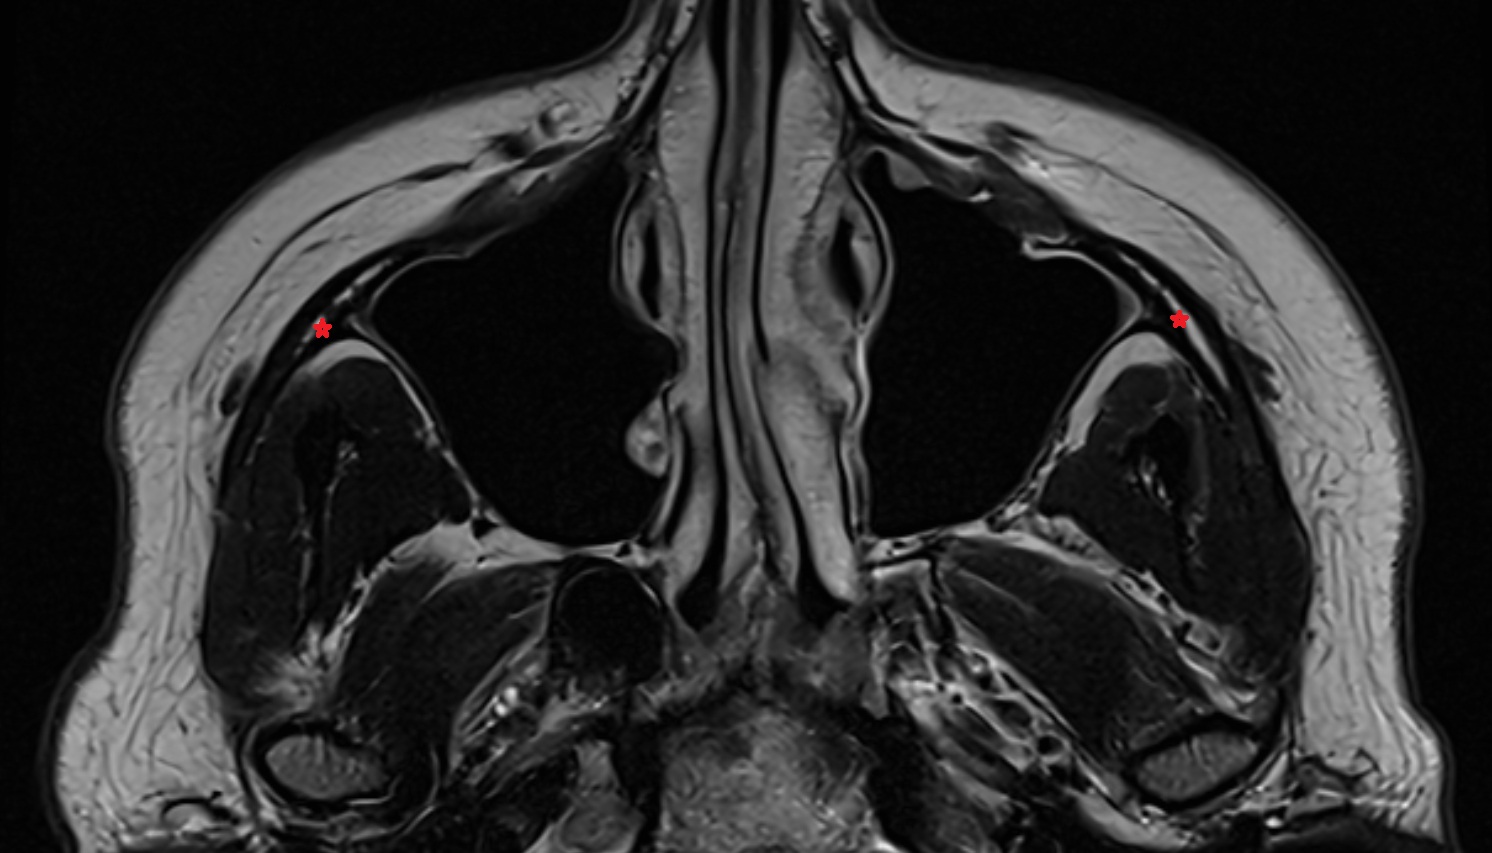

- Mandibular condyle

- Mandibular fossa

- Anterior Band of Articular Disc TMJ

- Posterior band of articular disc, TMJ

- Articular disc of temporomandibular joint

- Articular eminence

- Intermediate zone of articular disc

- Temporomandibular joint